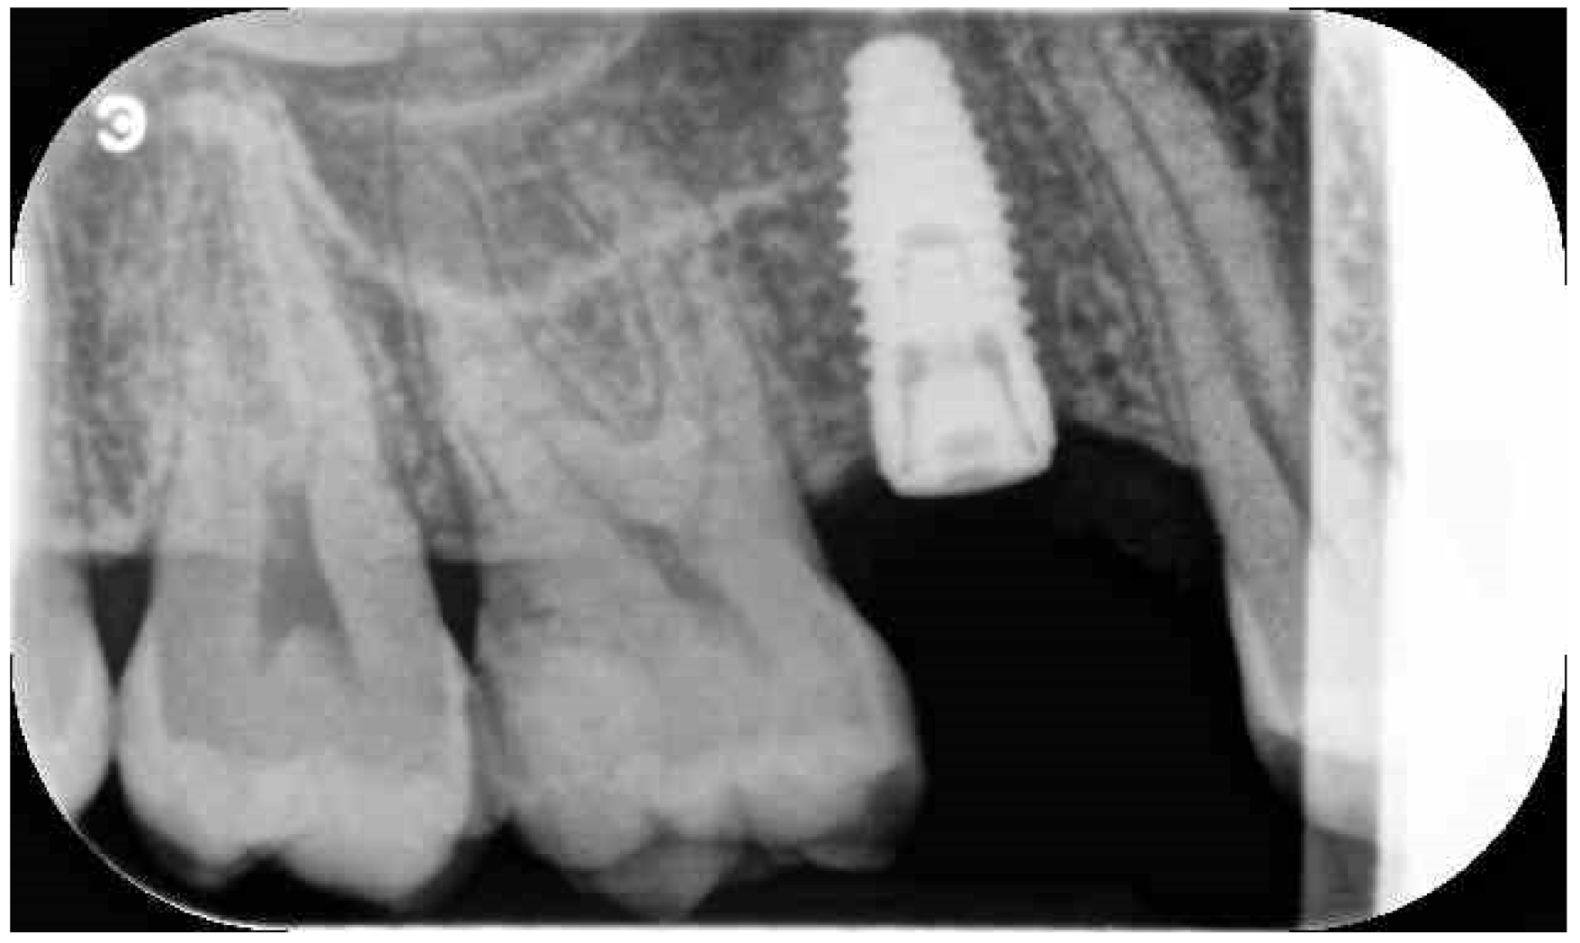

Before surgery, all patients underwent professional oral hygiene with periodontal treatment and supportive therapy, if needed. At the end of the prevention phase, the patients were moved to a careful home and professional oral-hygiene maintenance. Radiographic examination, including periapical radiographs (Figure 1), and computer tomography or CBCT scans, were also performed. All the implants were placed according to a predefined protocol, which includes antibiotic prophylaxis with amoxicillin clavulanate 1 gr every 12 h for six days, starting from the day of the surgery, following by a rinse with 0.2% chlorhexidine (CHX) solution for 1 min. Local anesthesia was performed with a 4% solution of articaine with epinephrine 1:100,000. All the implants were inserted after crestal and intrasulcular incisions performed to raise a mucoperiosteal flap. All the implants were 4.3 mm of diameter (Nobel Replace CC PMC Tapered, Nobel Biocare, Zurich, Switzerland), with 0.75 mm of machined collar. The implant sites were prepared using the lance drill of 1.5 mm of diameter to sign the implant position. Then the twist drill of 2 mm of diameter was used to reach the sinus floor cortex with a drill stop positioned 0.5 mm below the maxillary sinus floor (working length), estimated by using the CT or CBCT scan. Finally, the narrow platform drill (made for 3.5 mm diameter implants, Figure 2) was used at the working length to underprepare the implant recipient site. A collagen matrix (Condress, Smith and Nephew, Agrate Brianza, Italy) was inserted in the prepared site and then the sinus floor was fractured with a calibrated osteotome of 3.5 mm of diameter (Nobel Biocare). At this point, graft material consisting of 0.5 g. of deproteinized anorganic bovine bone, in small microgranules of 0.25–1 mm (Bio-Oss, Geistlich Pharma, Switzerland), mixed with sterile saline, was compacted into the sinus using the same osteotome, up to the working length (Figure 3). At the end of this procedure, all the implants were inserted according to a one-stage protocol [28,29], reaching a primary implant stability from 30 to 50 Ncm. All the implants were 8 to 10 mm of length (Figure 4), depending of the residual bone height. After implant placement, all the patients received oral and written recommendations about the correct maintenance, oral hygiene (i.e., mouthwash 0.2 CHX solutions twice a day, no brushing implant areas), and soft diet. Patients were also instructed to avoid any increase of the intrasinus pressure. The postoperative analgesic treatment was performed with ibuprofen 600 mg, as needed, but a maximum every eight hours for two to three days after the intervention. About two weeks after surgery, sutures were removed.

Figure 3.

Osteotome crestal preparation. Occlusal view.